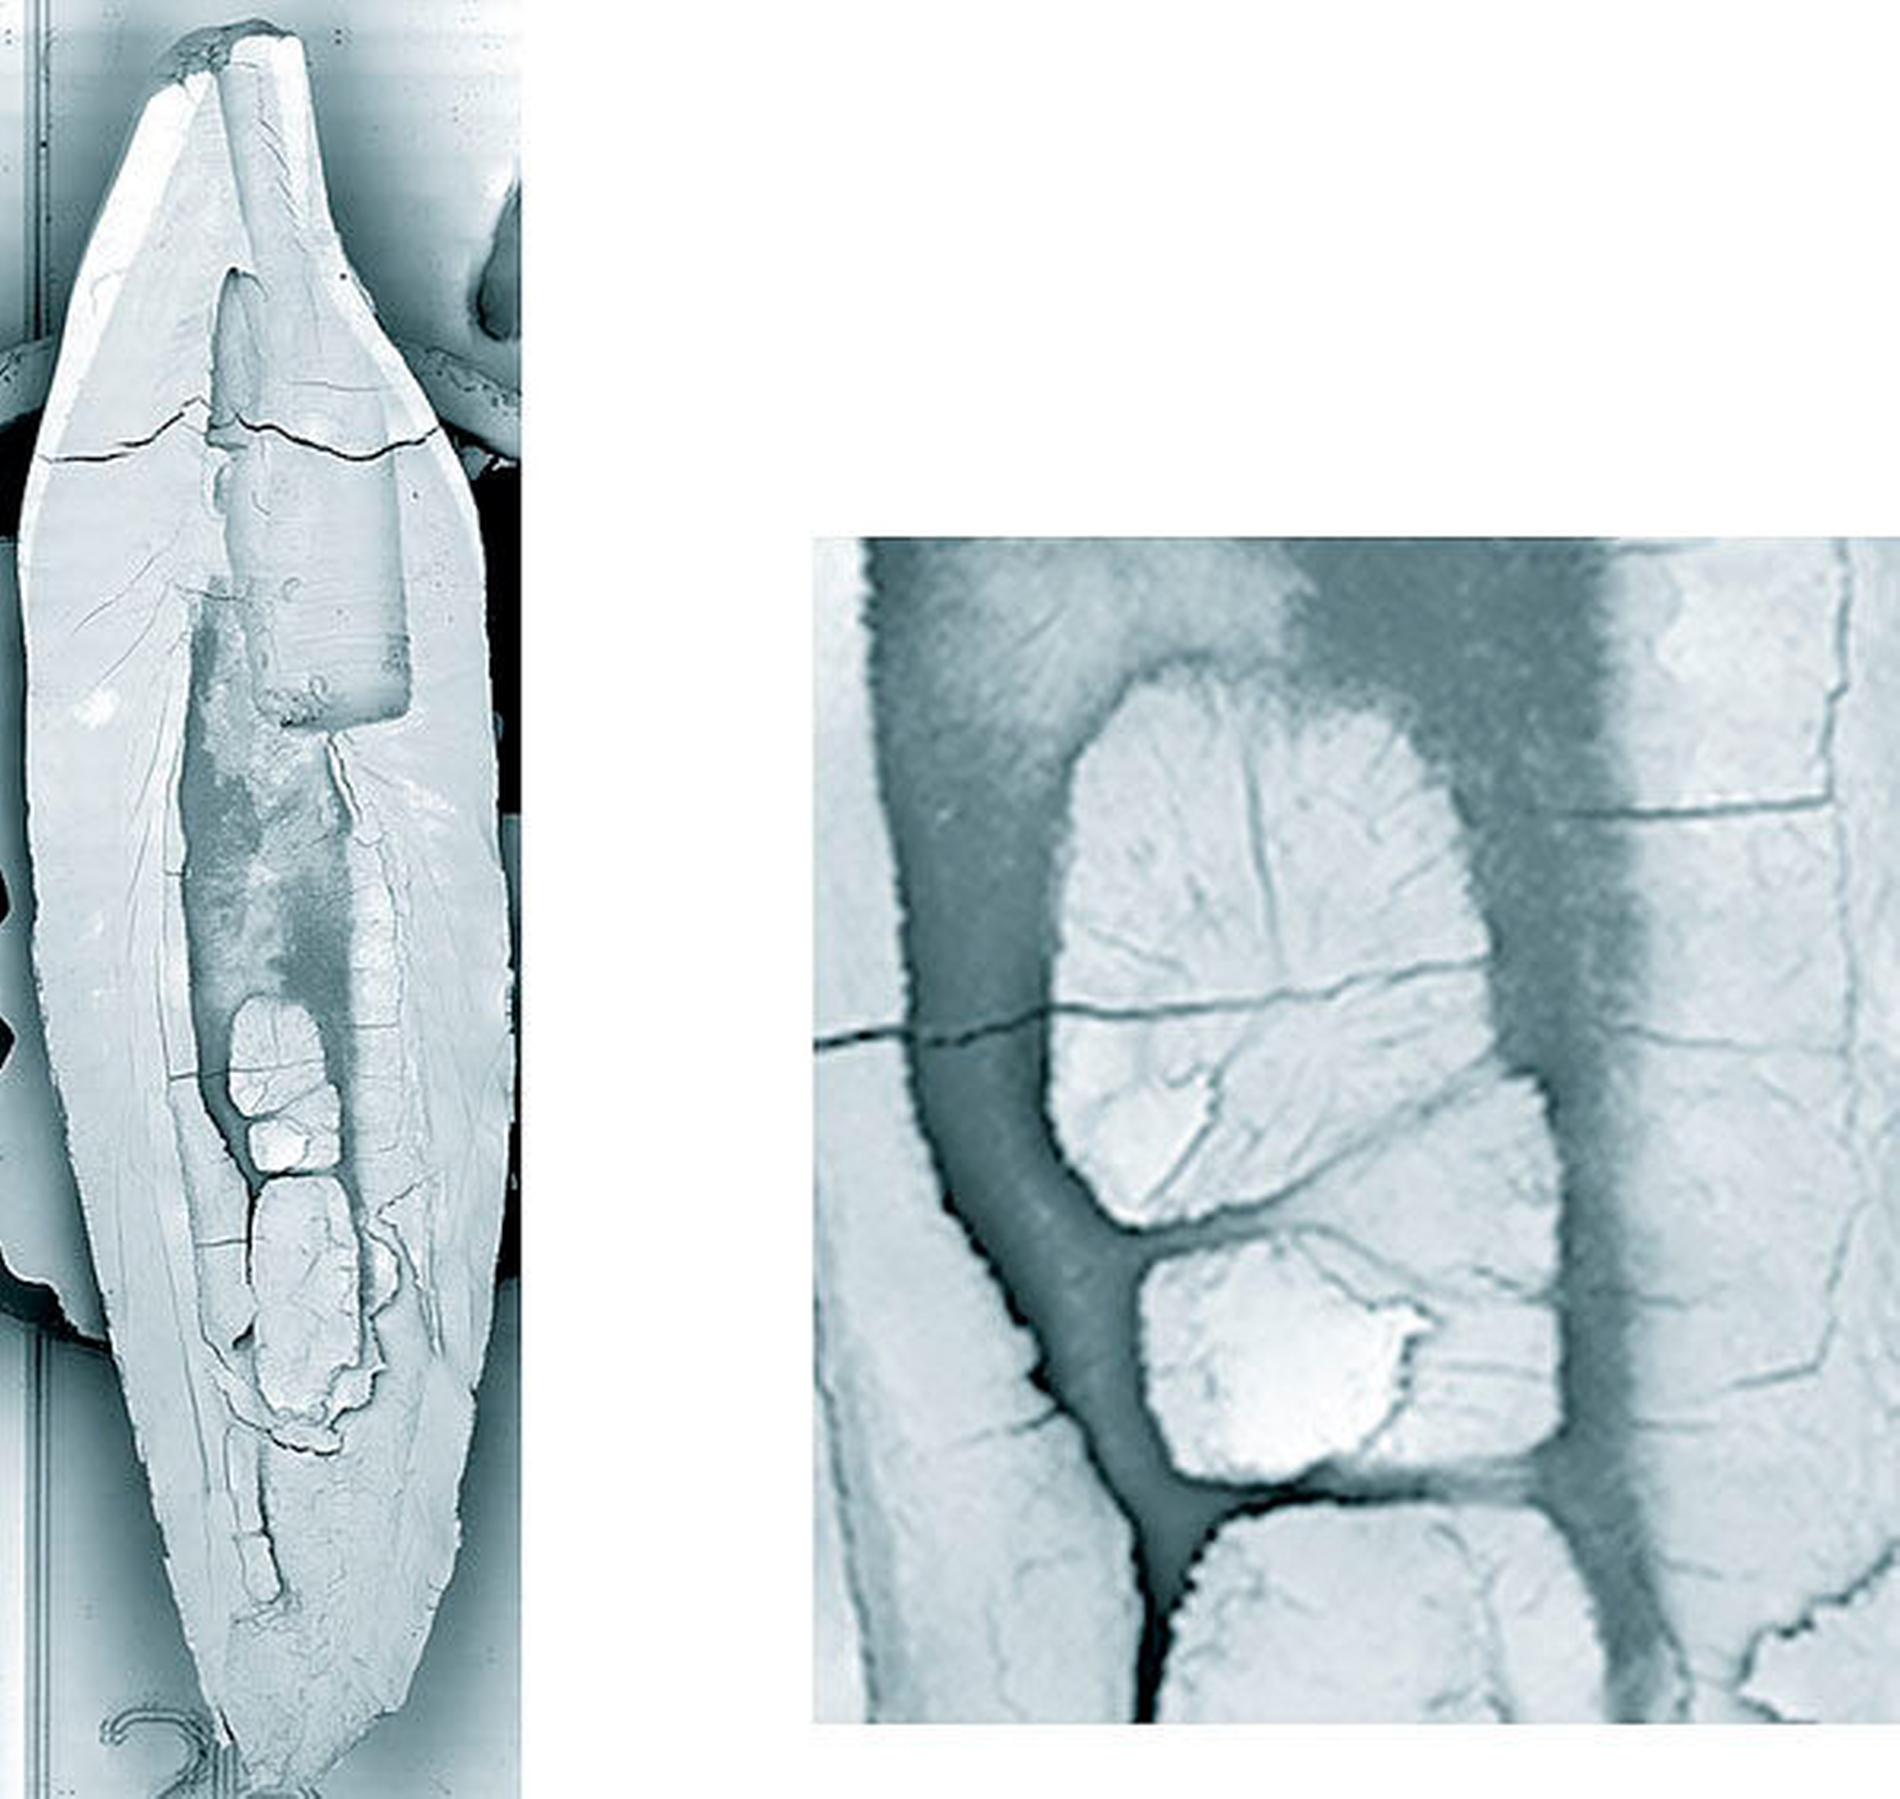

Erste Beschreibungen zur Anatomie menschlicher Wurzelkanalsysteme liegen von Carabelli aus dem Jahr 1844 vor. 1870 beschreibt Mühlreiter nicht nur die äußere Form, sondern weist auf die Besonderheit der Aufteilung in zwei Wurzelkanäle innerhalb der Wurzel hin. Es folgten vor allem Untersuchungen zur Anatomie des Wurzelkanalsystems mit der Transparenzmethode [Hess, 1917; Vertucci, 1984]. Hierbei wird in unterschiedlichen Verfahrensschritten das Dentin entkalkt und getrocknet. Nach einer Farbinjektion in das Wurzelkanalsystem wurde das Dentin transparent gemacht. Die dann zumeist sehr anschaulichen Präparate wurden als Grundlage zur Beurteilung der Anzahl der Wurzelkanäle und zum Verlauf genutzt (Abbildung 3).

Der Goldstandard für In-vitro-Untersuchungen bleibt die histologische Untersuchung am Hartgewebeschliff oder Serienschnittpräparat (Abbildung 5). Das Bruchpräparat unter Sicht mit dem Rasterelektronenmikroskop liefert dreidimensionale Eindrücke der variablen Anatomie des Wurzelkanalsystems von dentalen Weich- und Hartgeweben (Abbildungen 6 und 7). Insbesondere die häufig mehrfach unterteilten Dentinbrücken können Nischen für eine mikrobielle Infektion unterhalten. Degenerative fibröse Veränderungen der Pulpa und adhärente Dentikel können das Wurzelkanalsystem so einengen, dass die scheinbar einfache Wurzelkanalbehandlung einer nahezu geraden Wurzel deutlich erschwert wird (Abbildung 8).